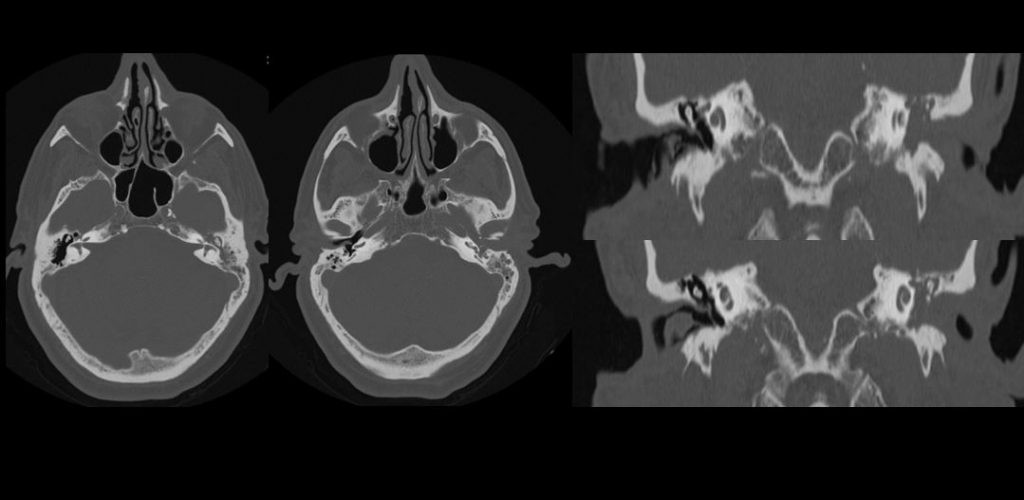

FIGURA 1 (TAC) a) Ocupación porción más medial de CAE izdo. por aumento de partes blandas que ensanchan canal, sin lograr visualizar la membrana timpánica b) Ocupación oído medio sin afectación de la cadena osicular. c) Erosión de tegmen timpani y  pared anterior de oído medio izdo., con solución de continuidad a fosa craneal media d) Erosión y dehiscencia de conducto óseo del nervio facial izquierdo a nivel de ganglio geniculado y erosión de pared posterior de la fosa glenoidea